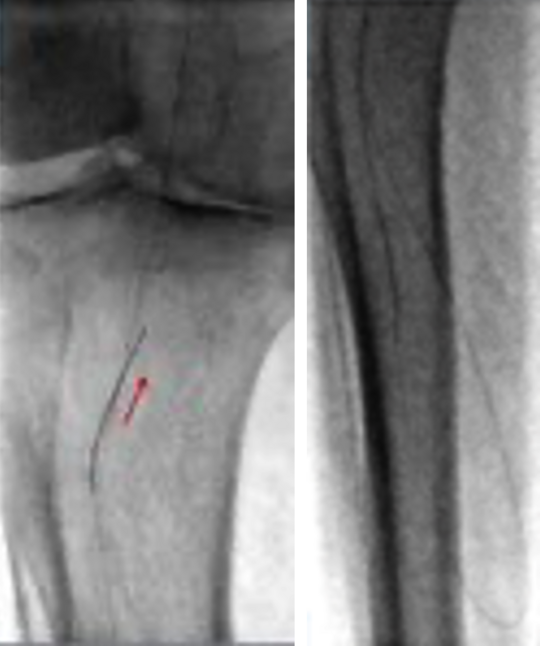

76-jährige Dame mit peripherer arterieller Verschlusskrankheit PAVK und Ruheschmerz (Stadium Fontaine 4), Katheter-Angiographie des Unterschenkels

Die Gefäßdarstellung zeigt komplexe Verschlüsse der direkten Fortsetzung der Arterie, die sich im Bereich der Kniekehle befindet, eine der beiden Hauptarterien des Unterschenkels und der lateralen (äußeren) Seite des Unterschenkels und des Fußes.

Eine Passage der Verschlüsse auf direktem Weg von vorwärts gerichtet ist nicht möglich. Daher erfolgt die rückwärts gerichtete Sondierung über ein Kollateralgefäß.

Danach gelingt die rückwärts gerichtete Passage der Verschlüsse.